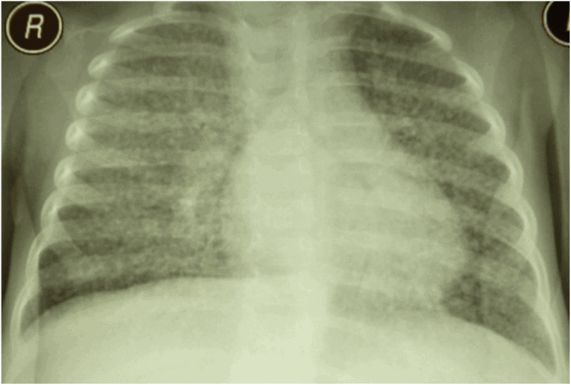

Рентгенологически в раннем периоде на обзорных рентгенограммах органов грудной клетки наш глаз воспринимает лишь непривычную рябь, обеднение легочного рисунка, четких же очажков при просвечивании еще не видно. Лишь через 1—2 нед после первых клинических проявлений заболевания на рентгенограмме грудной клетки видно густое равномерное высыпание по обоим легочным полям мелких очажков, не превышающих 2—3 мм в диаметре. Мелкие очаги при детальном их рассмотрении, лучше в области межреберных промежутков, отличаются однотипностью, расположены отдельно друг от друга, имеют довольно ясные очертания. Они мешают отображению нормального легочного рисунка, а также рисунка и формы корневых теней (рис. 8.13).

Рис. 8. U. Обзорная рентгенограмма органов грудной клетки с милиарным туберкулезом легких у ребенка одного года и б месяцев

В процессе наблюдения могут выявляться экстрапульмональные очаги в костной системе, почках и других органах. Иногда наблюдается плеврит. Помогают в диагностике поражений различных внутренних органов компьютерная томография или ультразвуковое исследование.

Рентгенография грудной клетки и другие методы визуализации, кожная туберкулиновая проба и IGRA также могут предоставить полезную диагностическую информацию. Рентгенография грудной клетки может указывать на признаки первичного или активного туберкулеза; при милиарном туберкулезе это видно по тысячам 2–3-миллиметровых интерстициальных узелков, равномерно распределенных по обоим легким.